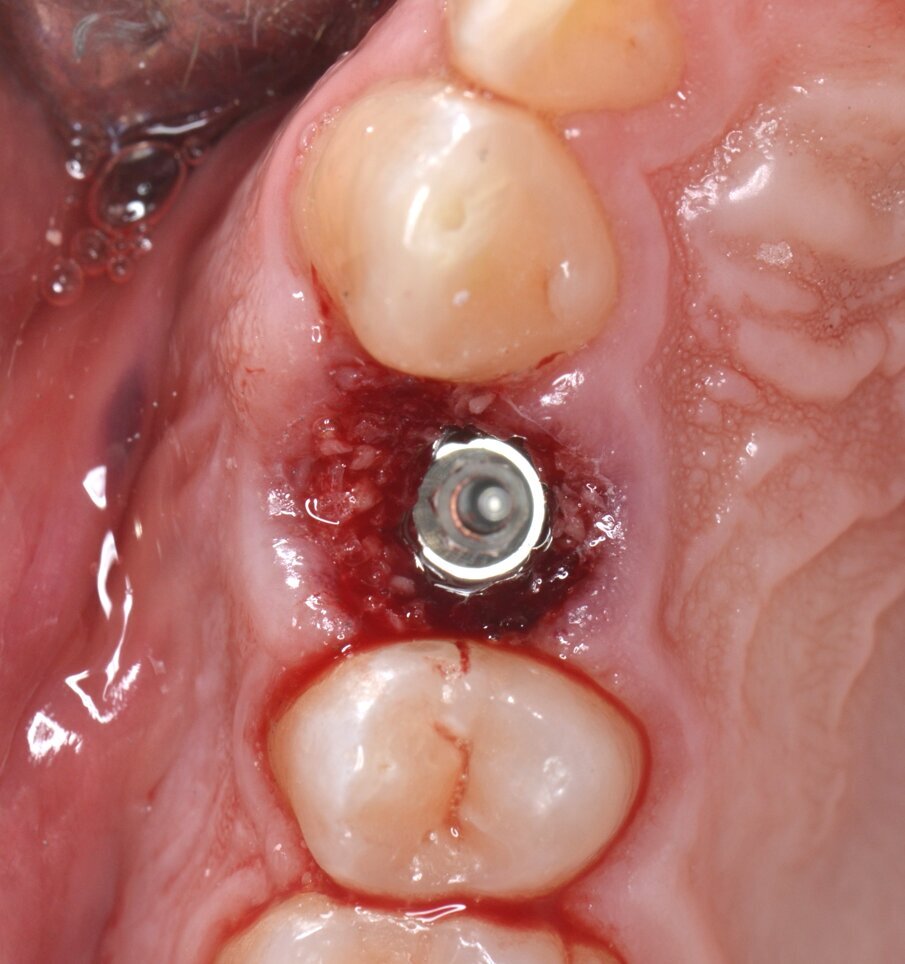

Viene inserito un impianto di tipo “bone level” da 3,5 x 15 mm: il raggiungimento di un torque di inserimento implantare (IT) superiore a 55 N.cm pone l’indicazione ad una procedura di provvisorizzazione immediata, motivo per cui un temporary abutment con una connessione protesica di tipo “platform switching” viene avvitato all’impianto con un torque di 35 N.cm (Figg. 10, 11). Per contrastare l’inevitabile contrazione dell’alveolo postestrattivo, il gap peri-implantare viene innestato con un biomateriale di origine eterologa (Figg. 12, 13). L’innesto viene eseguito con un leggero overbuilding in senso verticale allo scopo di sostenere il margine gengivale (Fig. 14).

Fig. 10 - Impianto inserito in posizione protesicamente corretta (IT > 55N.cm).

Fig. 11 - Moncone provvisorio serrato a 35 N.cm.